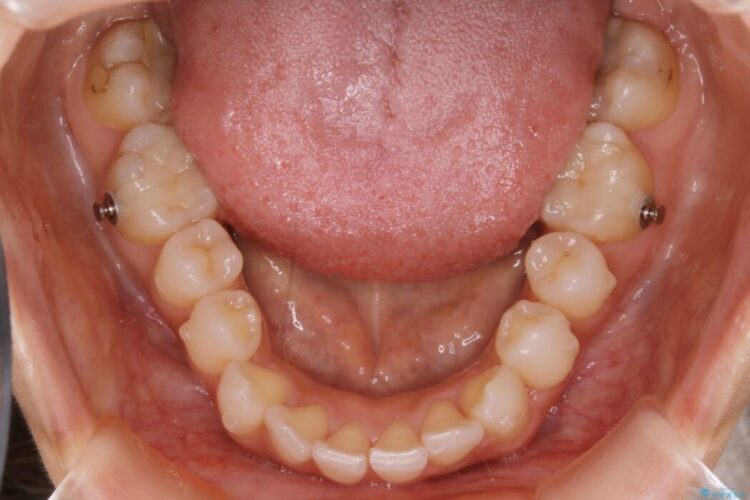

軽度のガタつきと不正咬合が見受けられましたので、インビザラインでの矯正治療を計画しました。

既定のインビザラインの装着時間を守っていただけたこともあり整ったアーチとなりました。

特に気にされていた噛み合わせは改善されご満足いただけました。

加えてインビザラインでの治療上設定されるアタッチメント(歯の表面に付けるプラスチックの突起)が外れやすい場合が多く、歯の移動に対する力が不足する可能性があります。